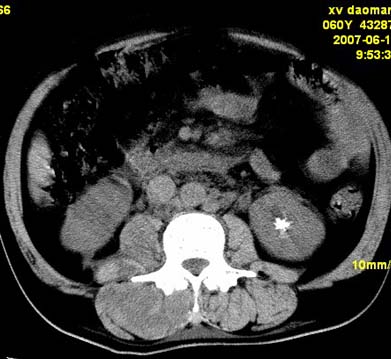

以下是引用还珠格格在2007-6-26 15:05:00的发言:[br]右侧腰大肌、同侧竖脊肌明显肿胀,呈不均匀密度减低影,右肾受压右上前移,脂肪间隙部分消失,另左侧肾盂内可见高密度影,是结石还是造影剂? 不知道病人用造影剂没有?考虑 右侧腰大肌及右侧竖脊肌寒性脓肿形成。[br][br][本贴已被 还珠格格 于 2007-6-26 15:21:35 修改过]

以下是引用小初学者在2007-6-26 15:42:00的发言:[br]1\\右侧腰大肌、同侧竖脊肌脓肿[br]2\\左侧肾盂结石

以下是引用刘明在2007-6-26 16:00:00的发言:[br][br]右侧竖直肌及腰大肌肿胀,脂肪间隙难辨,腹膜后血管旁见多个肿大淋巴结影,椎体附件右侧有压迫吸收、未见硬化迹象,考虑椎旁冷脓肿可能[br]左侧肾盂内可见高密度影,周围有毛刺,本图象是平扫,不是增强,应该是结石[br]